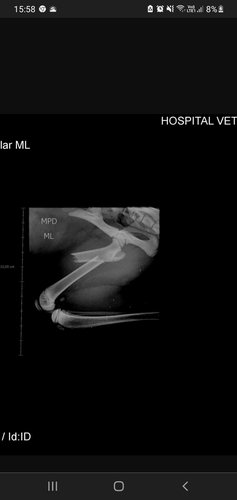

Eu sou a Luana dona da Jasmin, ela sofreu um acidente em casa, a tábua de passar roupa caiu em sua perna ocasionando que quebrou o seu fêmur. Peço a ajuda de vocês pois estou desesperada ela precisa ser operada o quanto antes.Será necessário placa ou gaiola em sua perna. No momento não estou tendo condições para arcar com essa situação.